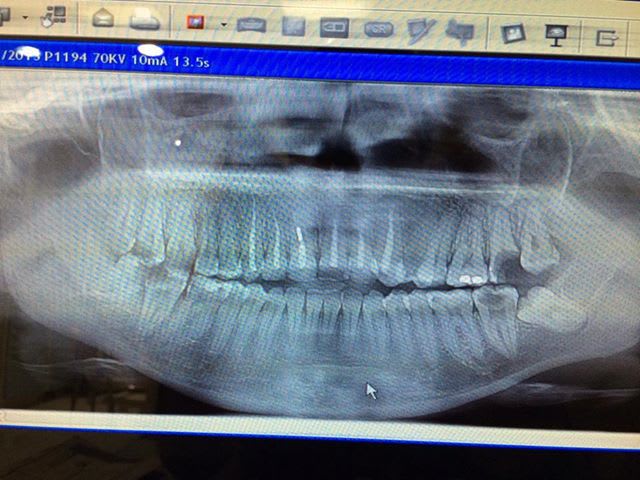

On essaye la "Magne" attitude ... LE No Post , No core , No Crown... dentistry ??? ;)....